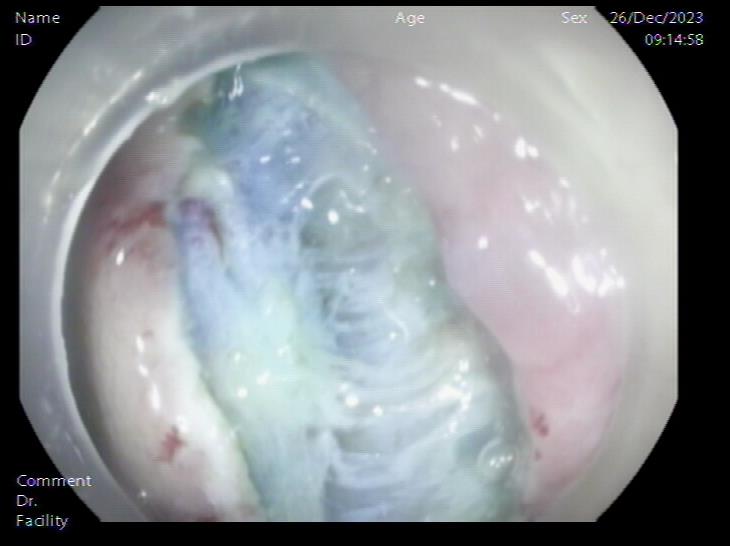

胃底SMT样隆起 内镜下切开刀行胃壁全层切开

患者,66岁,女性,平素身体健康,以“发现胃肿物2年余”主诉入院,既往于外院行电子胃镜检查发现胃底隆起,直径约1.5-2.0cm,超声内镜检查考虑黏膜下来源间质瘤可能,不除外壁外病变压迫。外院CT提示胃底浆膜下囊性病变可能。患者及家属诊治心切,辗转数家医院后为求内镜下治疗遂来二附院。入院后在消化内科再次超声内镜检查,提示胃壁增生病变可能,增强CT提示胃底胃壁增厚,结合内镜检查。患者及家属强烈要求内镜下探查及病变切除术。术前在王进海主任的指导组织下,进行了专业组内及多学科讨论,与患者及家属充分沟通后,决定行内镜下切开探查及病变治疗术,必要时可行内镜-腹腔镜联合手术(LECS)。邹百仓教授带领内镜下肿瘤诊治及超级微创手术团队施行手术,术中逐层切开胃壁黏膜层及黏膜下层,暴露固有肌层,未发现胃壁病变,遂切开胃壁全层,局部腹腔探查,切口附近腹腔内似韧带组织上发现半球形隆起,表面透亮光滑,大小约1.5X1.5cm,术中请外科李军辉及袁庆攻教授会诊后确诊为囊性病变,讨论后建议可以观察或内镜切开引流,与患者家属沟通后家属强烈要求切开引流,遂用内镜切开刀切开囊肿,引流少量清亮囊液,囊肿塌瘪,观察囊肿切口及局部无出血,切除局部部分胃壁组织送检,内镜下严密关闭切口,留置胃管后,返回病房,常规对症治疗1周,患者无并发症发生,正常出院。